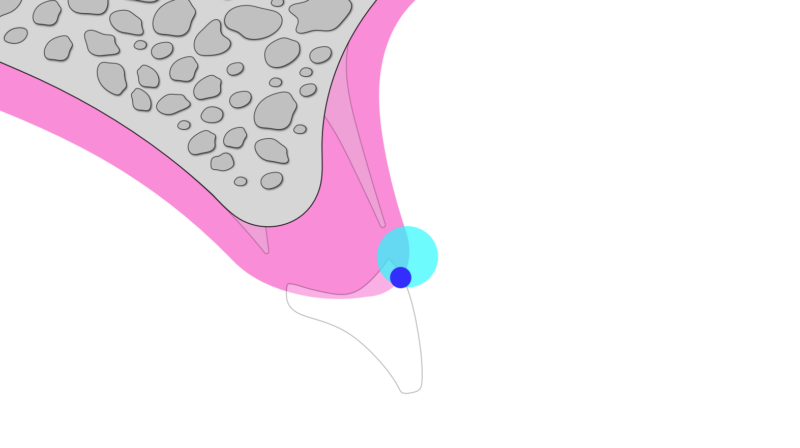

そこで近年注目されているのが、「抜歯と同時にインプラントを入れる方法」です。さらに、歯の一部をあえて残すことで歯肉や骨の形を維持する「ソケットシールドテクニック(SST)」という手法もあります。これにより、組織の吸収を最小限に抑え、より自然な仕上がりが期待できます。

①向かってる左のすぐにインプラントが可能な部分にはSSTを併用し、できるだけ負担の少ない治療を選択。